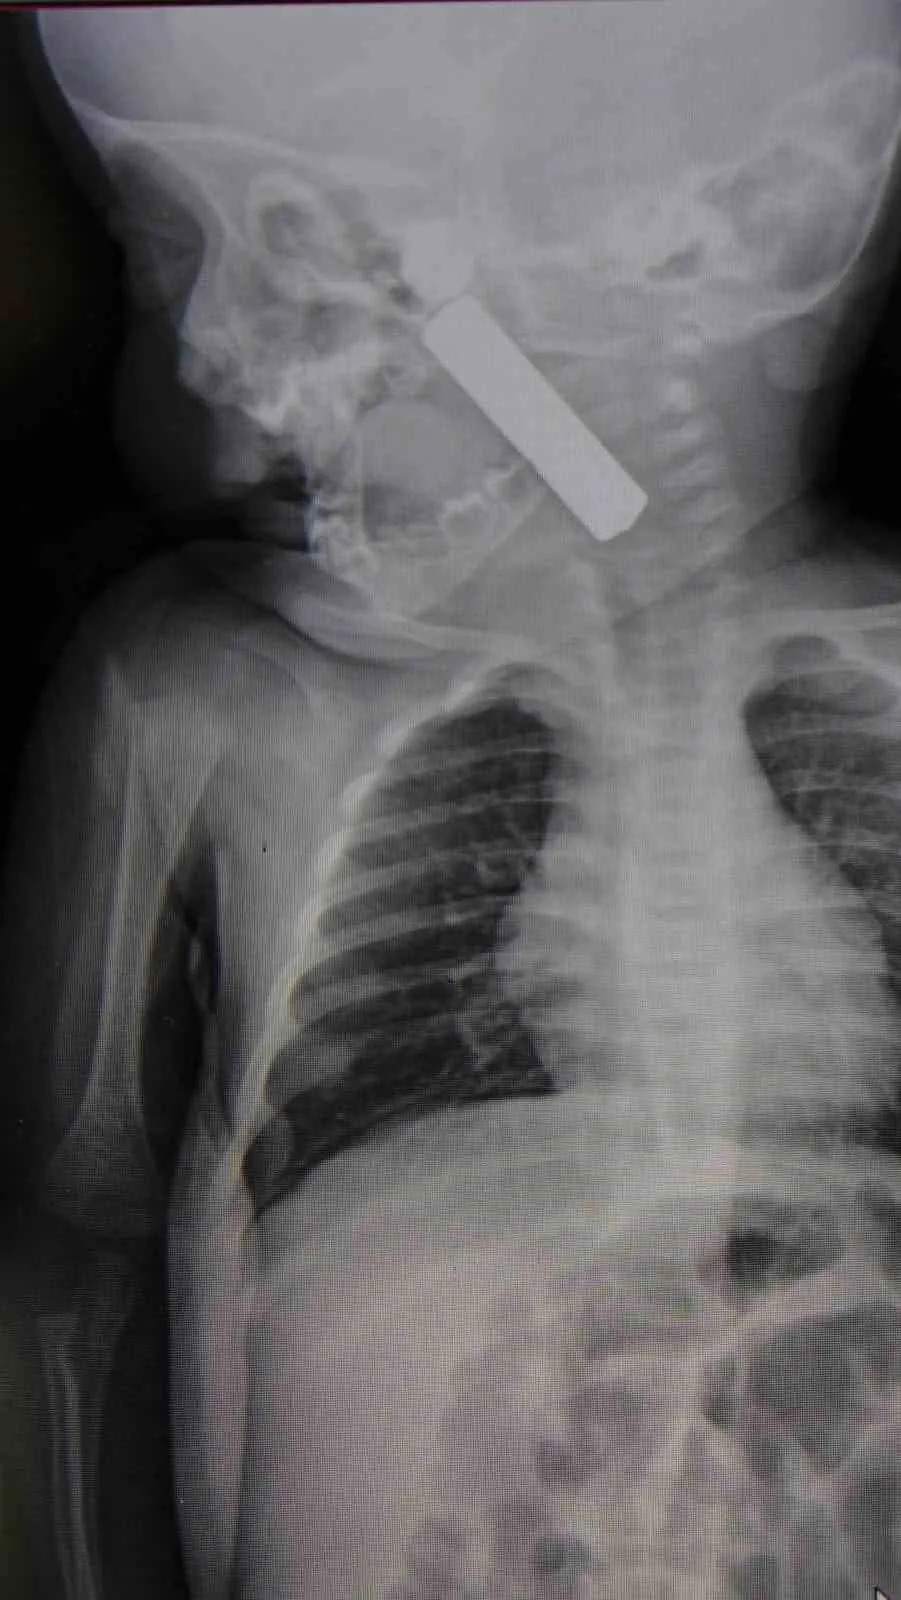

Karaman’da kusma ve solunum sıkıntısı şikâyetiyle hastaneye getirilen 6 aylık bebeğin boğazına kaçan kumanda pili, yapılan acil müdahale ile çıkarılarak hayati tehlike önlendi.

Karaman’da 6 aylık bebeğin boğazına kaçan kumanda pili, ameliyatla çıkarıldı. Edinilen bilgiye göre, kusma şikayeti ile ailesi tarafından Karaman Eğitim ve Araştırma Hastanesi acil servisine getirilen 6 aylık E.A. isimli kız bebeğin, yapılan muayene ve tetkiklerde boğazında kumanda pili kaçtığı tespit edildi. Solunum sıkıntısı da yaşayan bebek hemen ameliyata alındı. Çocuk Cerrahisi Uzmanı Doç. Dr. Mehmet Uysal tarafından yapılan ameliyatla bebeğin boğazındaki pil çıkarıldı. "Hemen müdahale ettik" Yaşanan olayla ilgili bilgi veren Doç. Dr. Mehmet Uysal, "Acil polikliniğimize kusma şikayeti ile 6 aylık bir kız bebek getirilmiş ve bize haber verildi. Biz de vakit kaybetmeden geldik, hastamızı gördük. Yapılan tetkikler sonucunda, ağız tabanına oturan ve yemek borusunun birinci darlığına kadar uzanan, kumanda pili dediğimiz bir pille karşılaştık. Filmde ve muayenede bunu gördük. Hastayı ilk gördüğümüzde bayağı siyanotik durumda, solunum sıkıntılıydı ve oksijen satürasyonu 90 civarındaydı. Böyle olunca bir an önce beklemeden hızlı bir şekilde ameliyathaneye götürdük. Orada ameliyathanedeki anestezi uzmanlarımız ve personel bize yardımcı oldu, hasta hızlı bir şekilde entübe edildi. Ondan sonra da laringoskop ve magill forseps dediğimiz malzemelerimizle bu yabancı cismi çıkarmış olduk. Bir an evvel müdahale ettik, iyi ki müdahale ettik, orada ağız tabanında, özellikle ön kısmında hasar oluşmuştu. Müdahale sonrasında da hastanın solunum problemleri bir süre devam etti, bu yüzden 24 saat takip ettik. Herhangi bir problem oluşmayınca 24 saat sonra kontrole gelmek üzere hastayı taburcu ettik" diye konuştu. "Aileleri uyarıyoruz" Ailelere uyarılarda bulunan Doç. Dr. Uysal, "Bu konularda aileleri uyarıyoruz. 1 yaş altı çocuklarda bile bu durum oluşabilir. Bazen 2-3 yaş diyoruz ama 1 yaş altındaki çocuklarda da emekleme döneminde bile bu tür yabancı cisimleri, özellikle kumanda pili, kalem pil gibi şeyleri ortada bırakmamak lazım. Çocuklar meraklı olduğu için her şeyi ağzına götürmeye meyilli. Dikkat etmediğimiz takdirde ölümcül sonuçlar oluşabiliyor. Bu vakada şanslıydık, çocuktaki durum erken fark edildi ve hemen müdahale edildi. Şu anda çocuk sağlıklı bir şekilde hayatına devam ediyor" dedi.